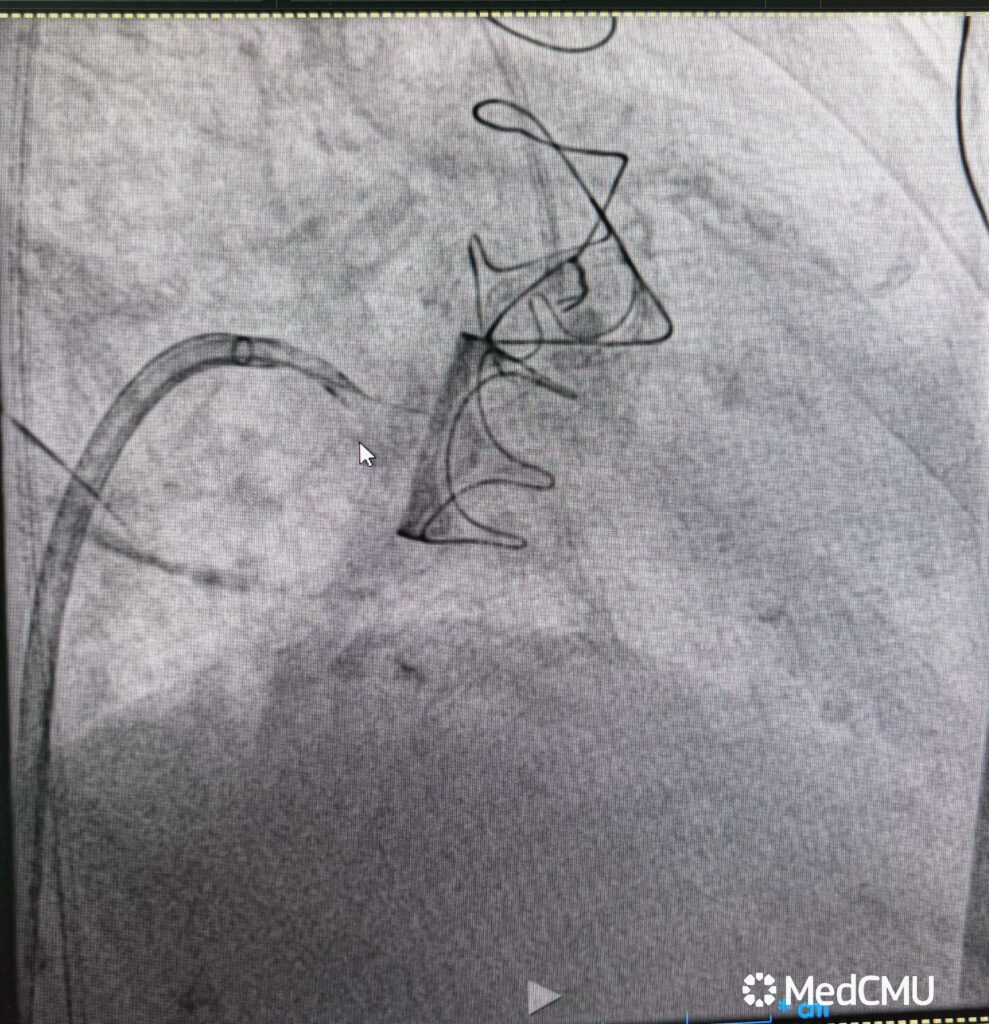

คณะแพทยศาสตร์ มหาวิทยาลัยเชียงใหม่ ประสบความสำเร็จในการรักษาผู้ป่วยหญิงไทย วัย 83 ปี ด้วยเทคนิคการเปลี่ยนลิ้นหัวใจไมตรัลเทียมตัวใหม่ แทนที่ตัวเก่าที่เสื่อมสภาพ ผ่านทางสายสวน โดยเทคนิคการตัดลิ้นหัวใจอันเดิม (LAMPOON – Laceration of the Anterior Mitral Leaflet to Prevent Outflow Obstruction) ถือเป็นรายแรกในระดับภูมิภาคของประเทศไทย ที่มีการทำหัตถการดังกล่าว และเป็นความก้าวหน้าสำคัญในการดูแลผู้ป่วยโรคหัวใจซับซ้อน

อ.พญ.ทรรศลักษณ์ ทองหงษ์ เปิดเผยว่า “เทคนิค LAMPOON ถือเป็นก้าวใหม่ของหัตถการในการรักษาภาวะแทรกซ้อนของการใส่ลิ้นหัวใจเทียม เนื่องจากต้องอาศัยความแม่นยำสูงในการเลาะพังผืดและกรีดลิ้นหัวใจเดิม เพื่อป้องกันการอุดกั้นทางออกของหัวใจ การทำหัตถการนี้ต่างจากการเปลี่ยนลิ้นหัวใจด้วยสายสวนแบบทั่วไป เพราะผู้ป่วยมีลิ้นหัวใจเทียมชนิดเก่าอยู่แล้วซึ่งเสื่อมสภาพจนทำให้เกิดภาวะแทรกซ้อน ซึ่งหากเป็นวิธีการเดิม ผู้ป่วยจำเป็นต้องรับการผ่าตัดเปิดทรวงอกซ้ำซึ่งมีความเสี่ยงสูงมาก แต่ในครั้งนี้ ทีมแพทย์สามารถทำได้สำเร็จ และผู้ป่วยฟื้นตัวได้โดยไม่ต้องเปิดทรวงอก ถือเป็นก้าวสำคัญในการดูแลผู้ป่วยหัวใจที่ซับซ้อน”